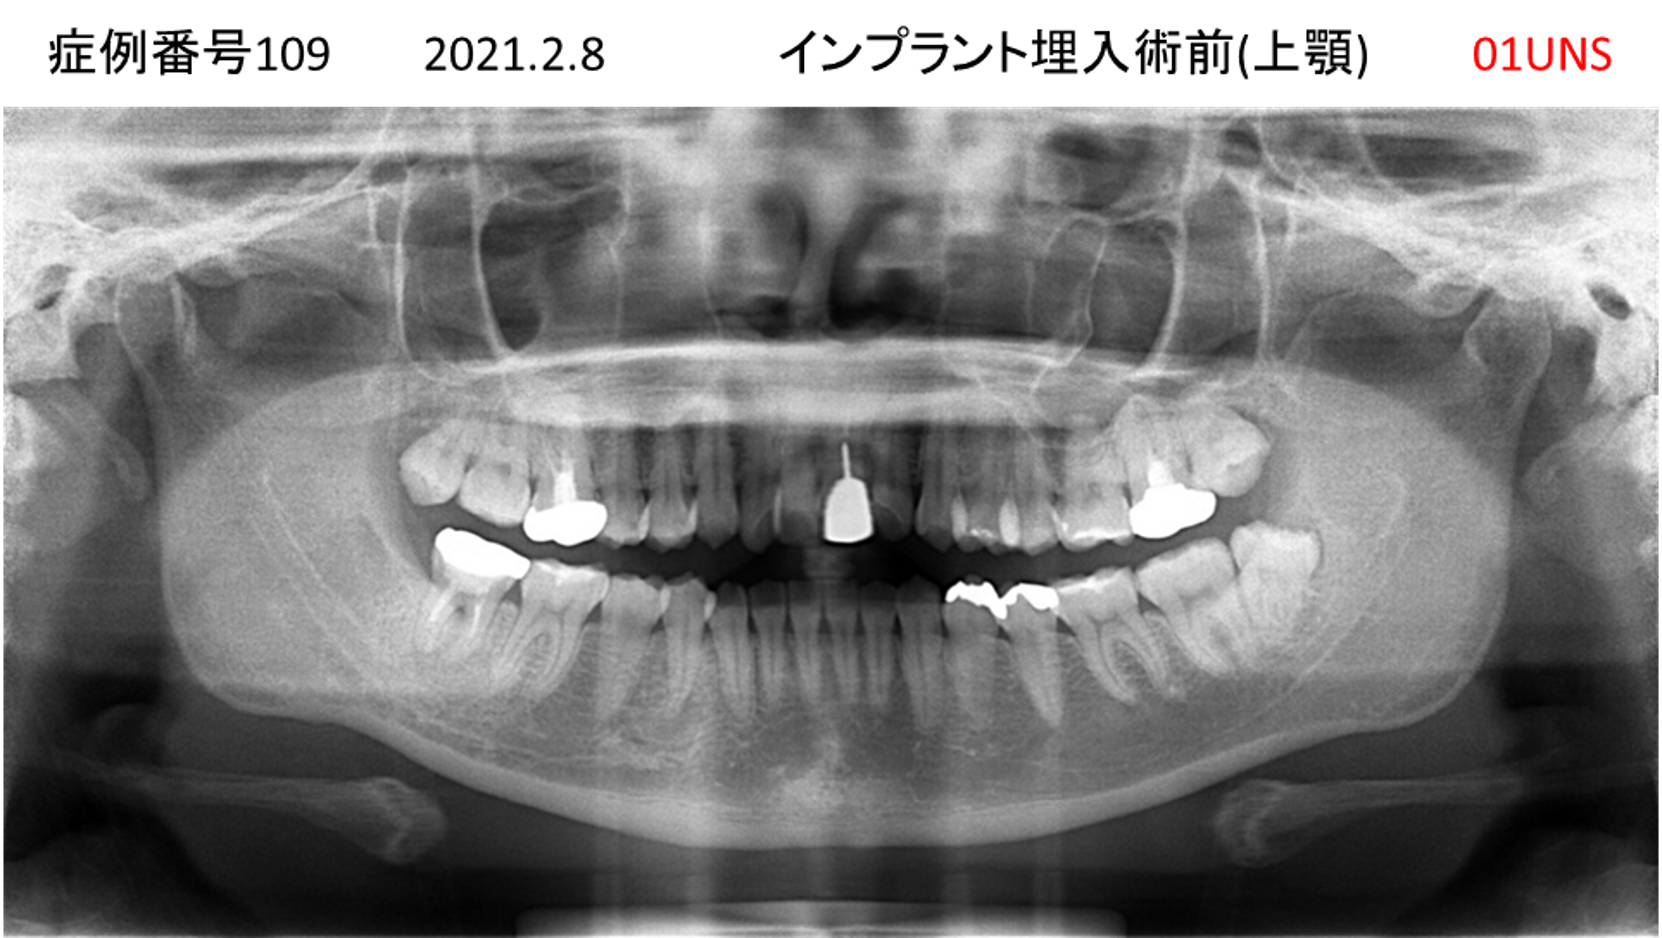

食事ができない/噛めない患者様のインプラント症例

| 治療名称 |

インプラント |

| 治療費用 |

540万円+税 |

| 治療期間 |

6か月 |

| 患者さんの症状(主訴) |

食事ができない。噛めない。上の前歯が揺れてきた。入れ歯がつらい。 |

| 治療内容 |

サイナスリフト、インプラント |

| 治療結果 |

なんでも食べられるようになった。力が入る(全身)ようになった。 |

| 治療の注意点(リスク/副作用) |

インプラントが壊れたら再治療が必要 |